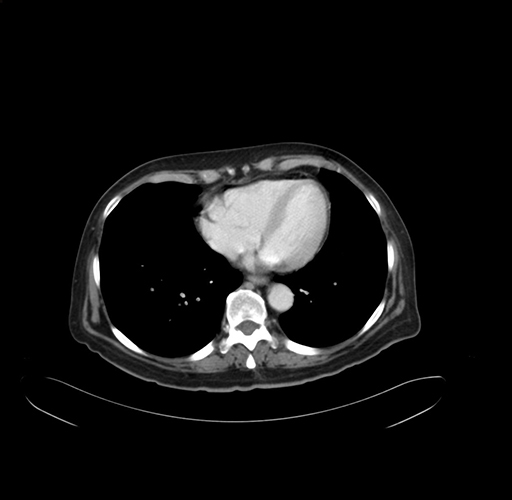

Pre-Chemo: Axial Venous

Axial Venous